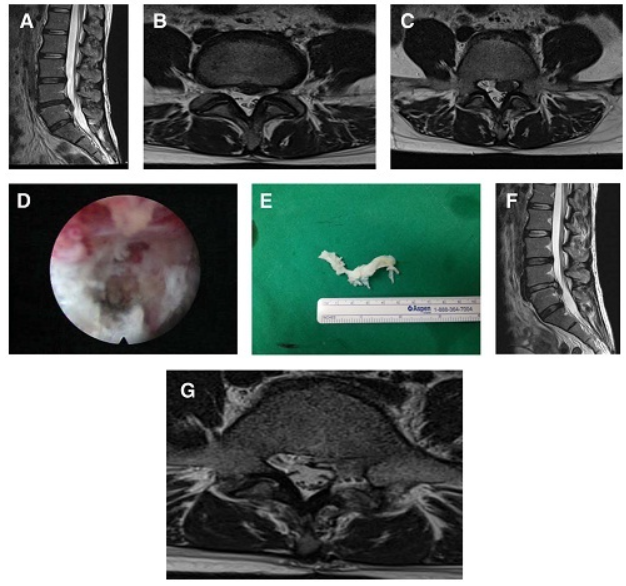

③腰椎磁共振(腰椎MRI)。

图片 14338

④经皮内镜下腰椎间盘切除术(PELD)

图片 14345 图片 14347

图片 14346